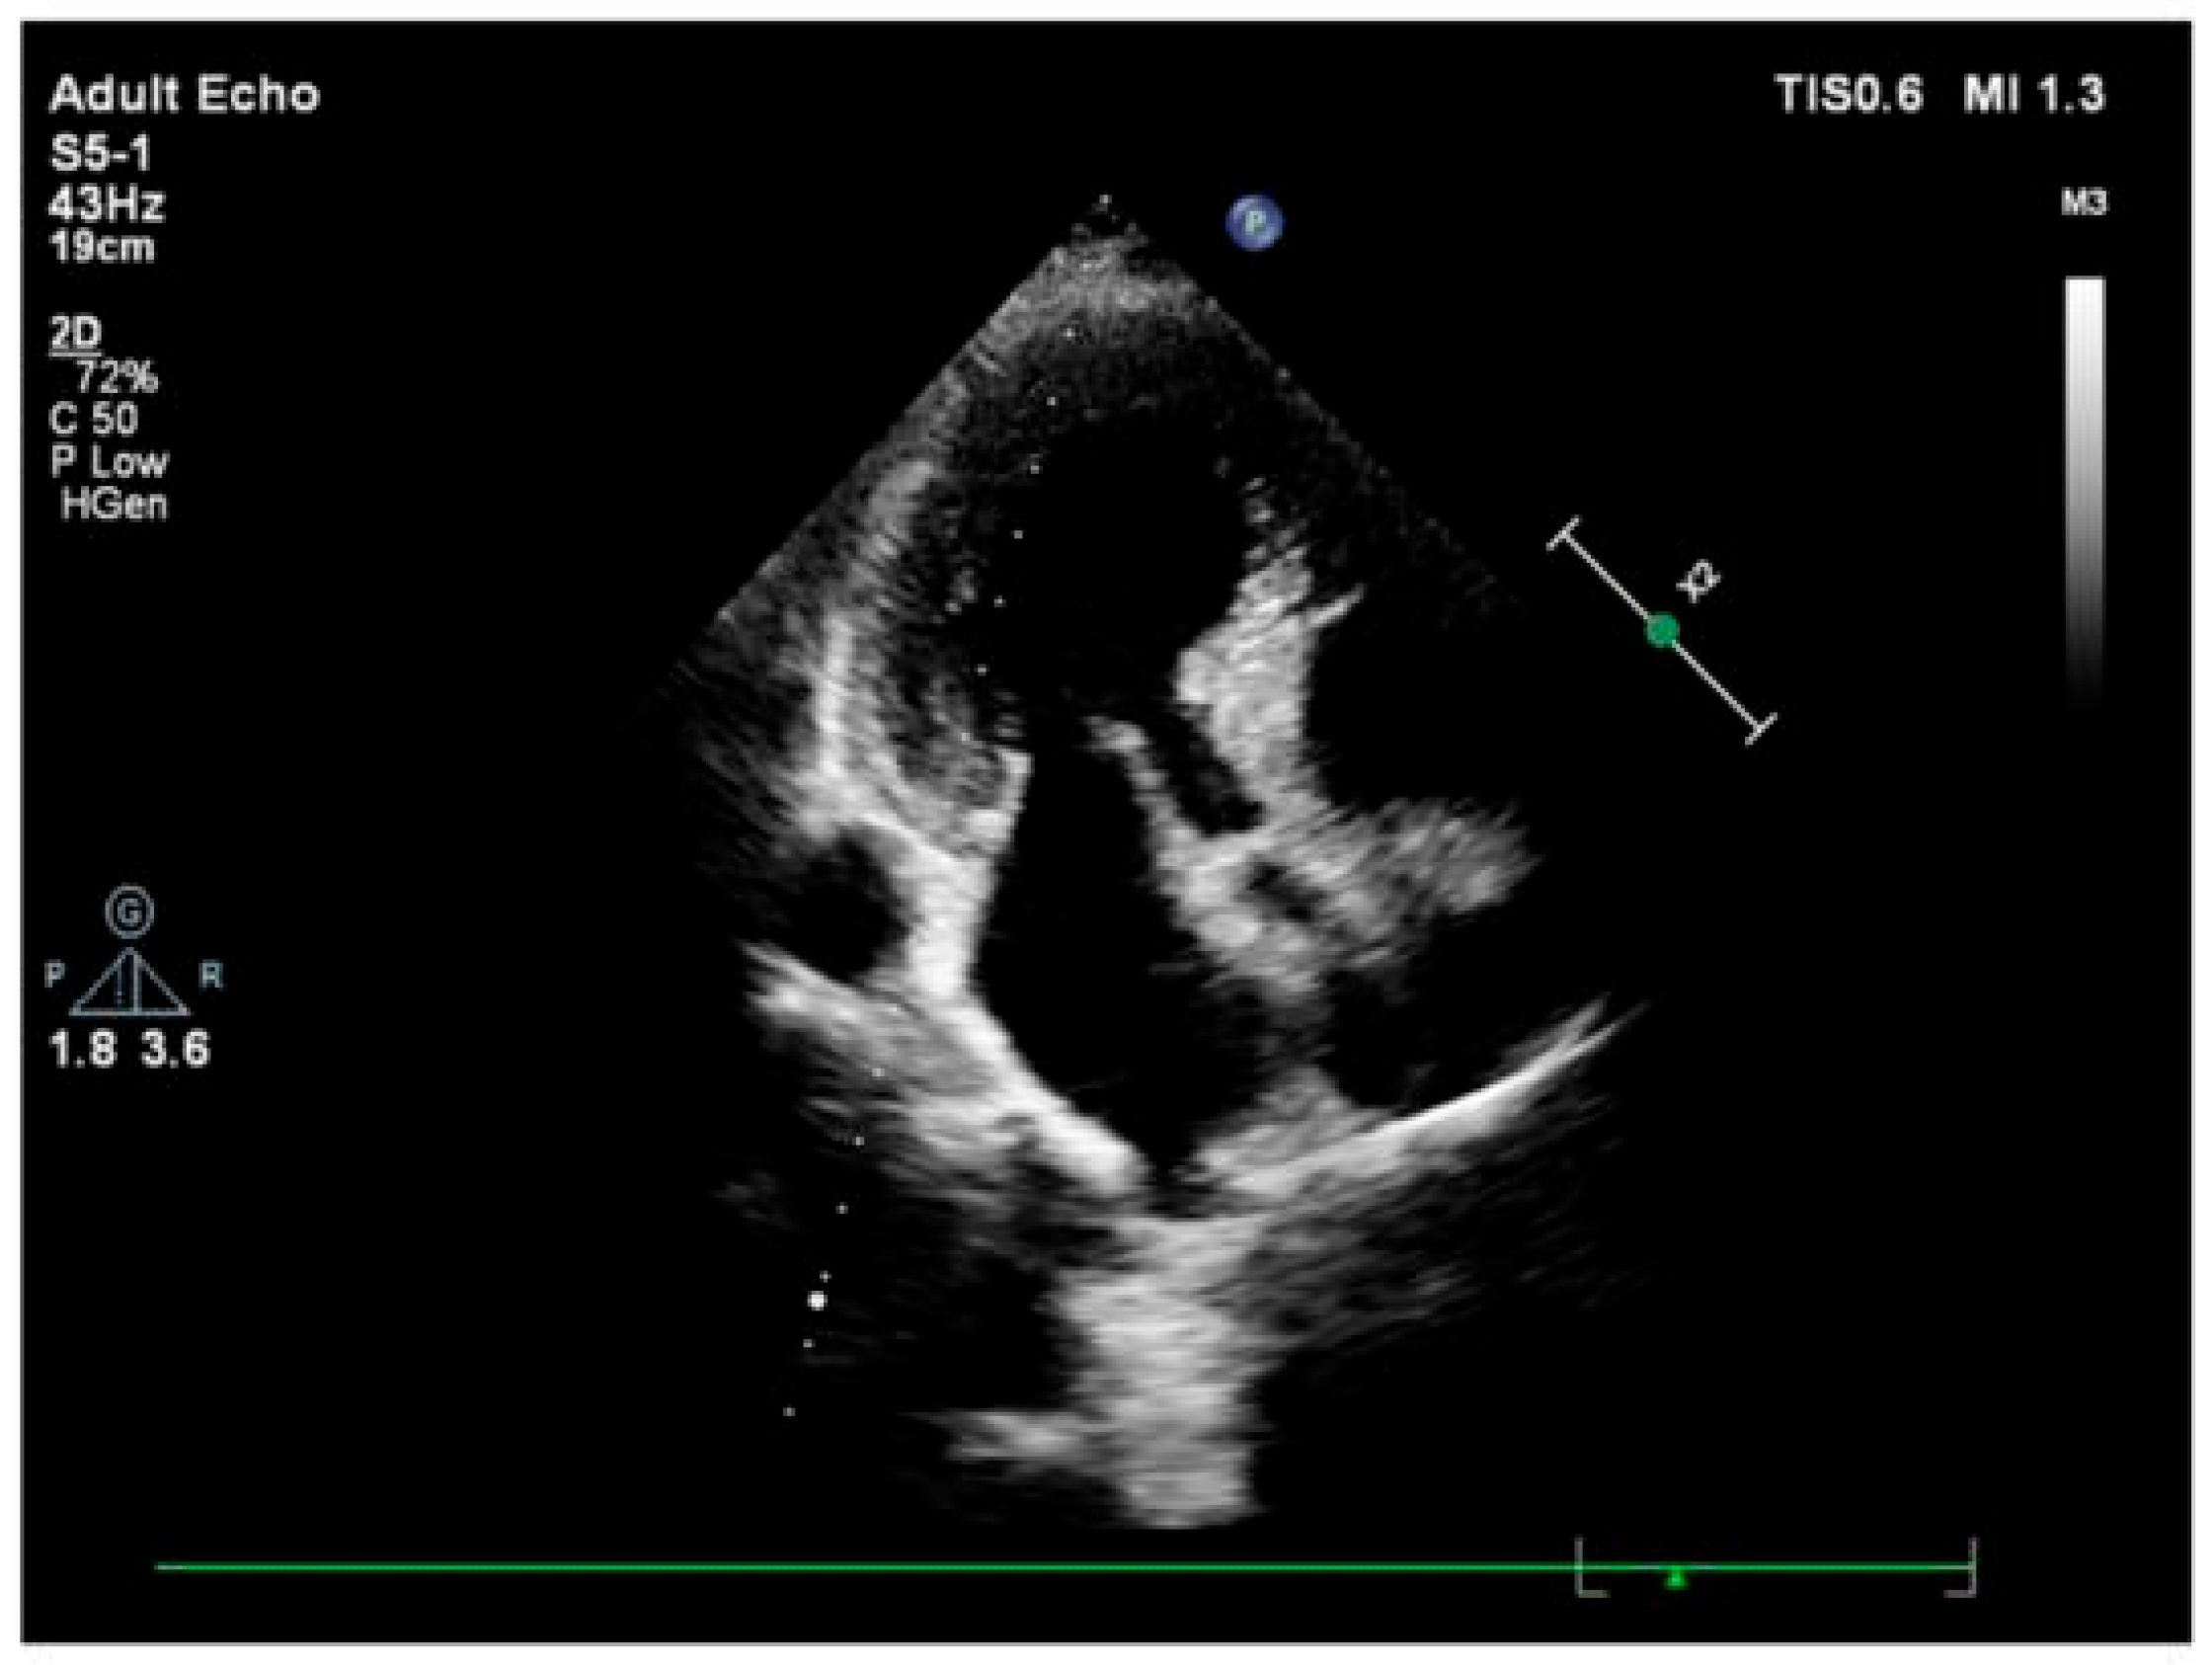

3.2. Imaging and Hemodynamic Observations

4.1. Repeated Acute Stress, Takotsubo Cardiomyopathy, and Stressed Heart Morphology

4.2. Perfusion Abnormalities and Segmental Remodeling Under Cumulative Chronic Stress